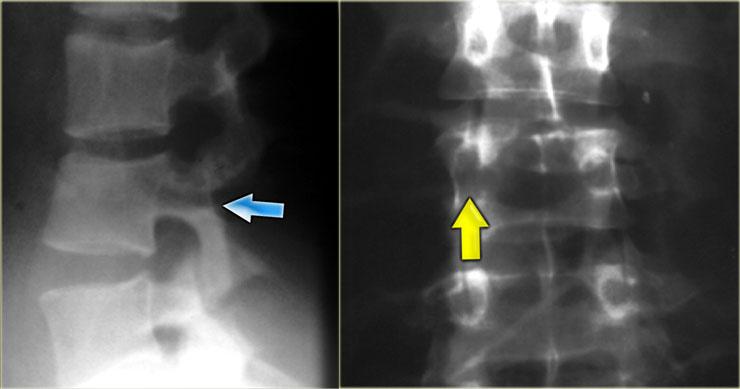

Bên trái là một ví dụ khác về gãy xương Chance.

Gãy xương Chance (3)

Bên trái là một biến thể gãy xương Chance.

Đây là tổn thương thuần túy dây chằng, tương tự như trật khớp liên mấu khớp hai bên, cũng là tổn thương thuần túy dây chằng.

Có đứt dây chằng gian gai, trật khớp mấu khớp và đứt ngang đĩa đệm.

Các biến thể thuần túy dây chằng và kết hợp xương / dây chằng có nguy cơ mất vững cao hơn so với loại xương đơn thuần.

Luôn tìm kiếm sự tách rời của các thành phần cột sống phía sau, giãn rộng đĩa đệm hoặc giãn rộng các mỏm gai và các khớp mặt.